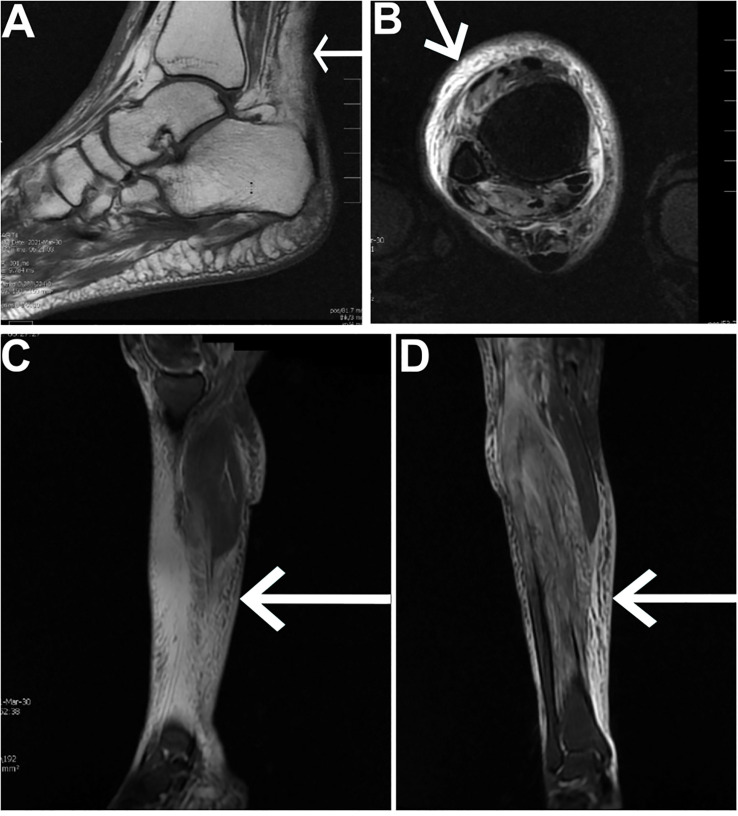

Case report: We present a 31-year-old woman with ESKD on hemodialysis and a history of type 1 diabetes who presented with recurrent, debilitating pain and swelling in the right lower extremity. Despite a comprehensive workup, including MRI and a muscle biopsy confirming myonecrosis, the patient's symptoms persisted despite conventional supportive care. Following a multidisciplinary discussion, corticosteroid therapy was initiated, resulting in dramatic symptom resolution within 48 h. The patient experienced significant pain reduction, improved mobility, and decreased swelling, allowing for discharge on a tapered steroid regimen. Notably, a subsequent recurrence of myonecrosis in a different muscle group also responded favorably to corticosteroid treatment, further underscoring its therapeutic potential in the management of patients with this condition.

Discussion/conclusion: This case underscores the importance of considering corticosteroids as an adjunctive therapy in refractory diabetic myonecrosis, particularly in patients who fail to respond to standard care. A detailed workup, a high degree of suspicion, distinct clinical findings, and imaging such as MRI, along with muscle biopsy, can accurately diagnose this condition. While corticosteroids are not routinely used due to their potential risks, their dramatic effect in this patient highlights the need for further research to better understand their role and to refine treatment strategies. By expanding the therapeutic approach to diabetic myonecrosis, this case provides valuable insights for improving outcomes in this rare and challenging condition. This case opens the door for the exploration of corticosteroids as an adjunctive therapy in similar diabetic patients with ESKD and refractory myonecrosis.